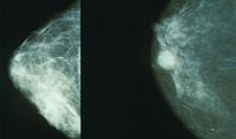

New Way to Image Dense Breasts

By Avatar

article

Dartmouth engineers and radiologists are developing new approaches for an emerging technique called MRI with near-infrared spectroscopy (NIRS) to  image dense breasts for abnormalities. The study will appear in the February 2014 issue of the journal Academic Radiology.